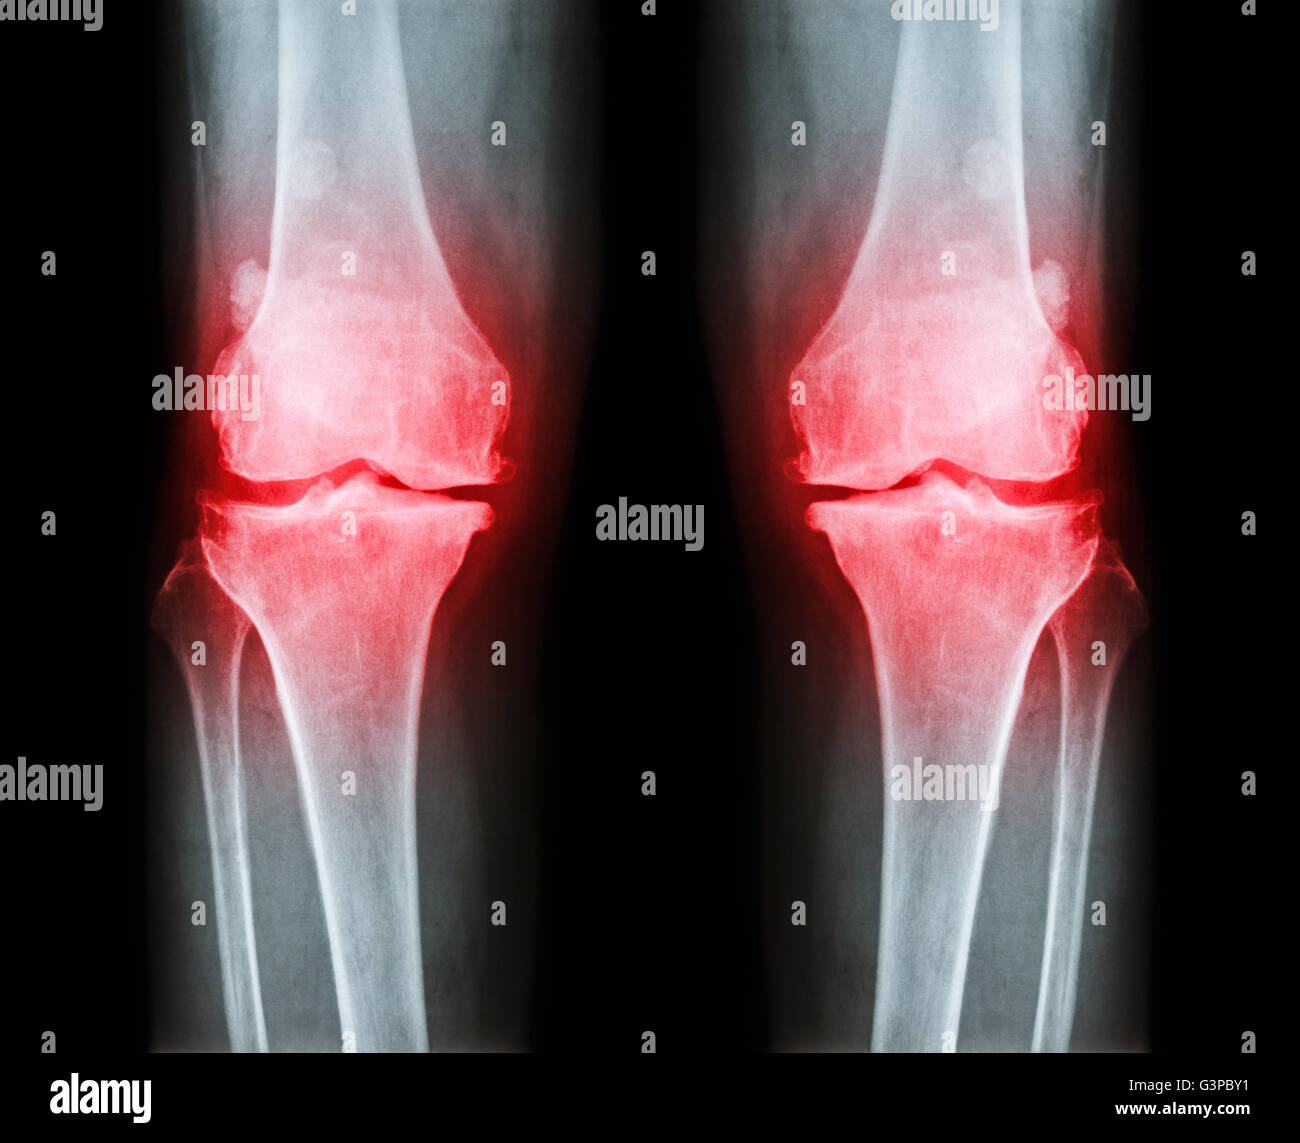

L'ARTHROSE DU GENOU Arthrose du genou ( ) ( Film x-ray à la fois avec l'arthrite du genou d'articulation du genou : articulation du genou espace ) ( Médecine et Sc Banque D'Imageshttps://www.alamyimages.fr/image-license-details/?v=1https://www.alamyimages.fr/photo-image-l-arthrose-du-genou-arthrose-du-genou-film-x-ray-a-la-fois-avec-l-arthrite-du-genou-d-articulation-du-genou-articulation-du-genou-espace-medecine-et-sc-86202577.html

L'ARTHROSE DU GENOU Arthrose du genou ( ) ( Film x-ray à la fois avec l'arthrite du genou d'articulation du genou : articulation du genou espace ) ( Médecine et Sc Banque D'Imageshttps://www.alamyimages.fr/image-license-details/?v=1https://www.alamyimages.fr/photo-image-l-arthrose-du-genou-arthrose-du-genou-film-x-ray-a-la-fois-avec-l-arthrite-du-genou-d-articulation-du-genou-articulation-du-genou-espace-medecine-et-sc-86202577.htmlRFF06T7D–L'ARTHROSE DU GENOU Arthrose du genou ( ) ( Film x-ray à la fois avec l'arthrite du genou d'articulation du genou : articulation du genou espace ) ( Médecine et Sc

L'ARTHROSE DU GENOU Arthrose du genou ( ) ( Film x-ray à la fois avec l'arthrite du genou d'articulation du genou : articulation du genou espace ) ( Médecine et Sc Banque D'Imageshttps://www.alamyimages.fr/image-license-details/?v=1https://www.alamyimages.fr/photo-image-l-arthrose-du-genou-arthrose-du-genou-film-x-ray-a-la-fois-avec-l-arthrite-du-genou-d-articulation-du-genou-articulation-du-genou-espace-medecine-et-sc-86202589.html

L'ARTHROSE DU GENOU Arthrose du genou ( ) ( Film x-ray à la fois avec l'arthrite du genou d'articulation du genou : articulation du genou espace ) ( Médecine et Sc Banque D'Imageshttps://www.alamyimages.fr/image-license-details/?v=1https://www.alamyimages.fr/photo-image-l-arthrose-du-genou-arthrose-du-genou-film-x-ray-a-la-fois-avec-l-arthrite-du-genou-d-articulation-du-genou-articulation-du-genou-espace-medecine-et-sc-86202589.htmlRFF06T7W–L'ARTHROSE DU GENOU Arthrose du genou ( ) ( Film x-ray à la fois avec l'arthrite du genou d'articulation du genou : articulation du genou espace ) ( Médecine et Sc

L'ARTHROSE DU GENOU Arthrose du genou ( ) ( Film x-ray à la fois avec l'arthrite du genou d'articulation du genou : articulation du genou espace ) ( Médecine et Sc Banque D'Imageshttps://www.alamyimages.fr/image-license-details/?v=1https://www.alamyimages.fr/photo-image-l-arthrose-du-genou-arthrose-du-genou-film-x-ray-a-la-fois-avec-l-arthrite-du-genou-d-articulation-du-genou-articulation-du-genou-espace-medecine-et-sc-86202573.html

L'ARTHROSE DU GENOU Arthrose du genou ( ) ( Film x-ray à la fois avec l'arthrite du genou d'articulation du genou : articulation du genou espace ) ( Médecine et Sc Banque D'Imageshttps://www.alamyimages.fr/image-license-details/?v=1https://www.alamyimages.fr/photo-image-l-arthrose-du-genou-arthrose-du-genou-film-x-ray-a-la-fois-avec-l-arthrite-du-genou-d-articulation-du-genou-articulation-du-genou-espace-medecine-et-sc-86202573.htmlRFF06T79–L'ARTHROSE DU GENOU Arthrose du genou ( ) ( Film x-ray à la fois avec l'arthrite du genou d'articulation du genou : articulation du genou espace ) ( Médecine et Sc

L'ARTHROSE DU GENOU Arthrose du genou ( ) ( Film x-ray à la fois avec l'arthrite du genou d'articulation du genou : articulation du genou espace ) ( Médecine et Sc Banque D'Imageshttps://www.alamyimages.fr/image-license-details/?v=1https://www.alamyimages.fr/photo-image-l-arthrose-du-genou-arthrose-du-genou-film-x-ray-a-la-fois-avec-l-arthrite-du-genou-d-articulation-du-genou-articulation-du-genou-espace-medecine-et-sc-86202580.html

L'ARTHROSE DU GENOU Arthrose du genou ( ) ( Film x-ray à la fois avec l'arthrite du genou d'articulation du genou : articulation du genou espace ) ( Médecine et Sc Banque D'Imageshttps://www.alamyimages.fr/image-license-details/?v=1https://www.alamyimages.fr/photo-image-l-arthrose-du-genou-arthrose-du-genou-film-x-ray-a-la-fois-avec-l-arthrite-du-genou-d-articulation-du-genou-articulation-du-genou-espace-medecine-et-sc-86202580.htmlRFF06T7G–L'ARTHROSE DU GENOU Arthrose du genou ( ) ( Film x-ray à la fois avec l'arthrite du genou d'articulation du genou : articulation du genou espace ) ( Médecine et Sc